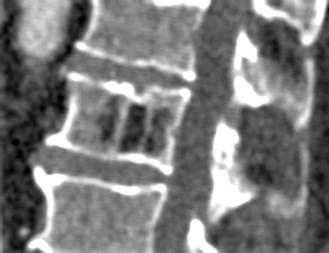

При КТ определяется участок в теле позвонка, в его дуге, ножках или суставных отростках, чаще всего имеющий форму шара или эллипсоида, или неправильную форму. Размеры гемангиомы различные - на томограммах можно можно опухоль начиная от 0,5 см. Редко встречаются гигантские сосудистые образования, занимающие практически весь объем позвонка. Рентгеновская плотность данного участка снижена по сравнению с плотностью губчатого вещества и, тем более, замыкательных пластинок.

На изображении представлен поперечный срез через позвонок. В теле позвонка - типичная гемангиома (H). Цифрой 1 отмечены утолщенные и разреженные трабекулы губчатого вещества, цифрой 2 - периваскулярные пространства, сосудистые лакуны. При компьютерной томографии они имеют низкую плотность, приближающуюся к плотности жира (гемангиолипома).

Типичная гемангиома в грудном позвонке. На аксиальном срезе - справа - отчетливо виден характерный «точечный» «рисунок», обусловленный утолщением трабекул и большим количеством периваскулярного жира.

Небольшая сосудистая опухоль в боковых отделах тела первого поясничного позвонка. При компьютерной томографии выявлен гиподенсный участок плотностью -25…-30 единиц Хаунсфилда, с типичными утолщенными и «разреженными» трабекулами губчатого вещества.

В зависимости от количества периваскулярного жира плотность гемангиомы может колебаться от +200 единиц Хаунсфилда до -40 и меньше, но практически никогда не достигает плотности жировой ткани (-100 единиц Хаунсфилда). В структуре опухоли видны множественные разреженные и утолщенные до 1-3 мм трабекулы, дающие характерный «мелкоточечный» рисунок на аксиальных срезах и «полосатый» рисунок на аксиальных и корональных изображениях. После введения контрастного вещества строма опухоли может усиливаться, зачастую весьма значительно. Наибольшую плотность сосудистые опухоли имеют в артериальную фазу контрастирования. Контраст из сосудистых лакун вымывается быстро, поэтому уже в венозную фазу плотность образования существенно снижается.